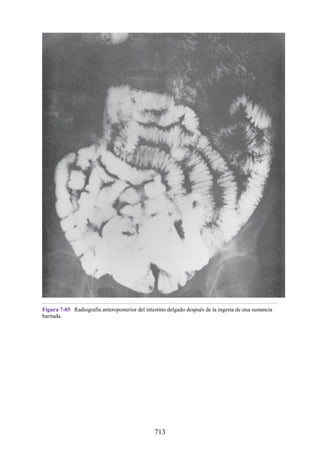

drena en las venas cefálica y basílica en sus extremos lateral y medial,

286